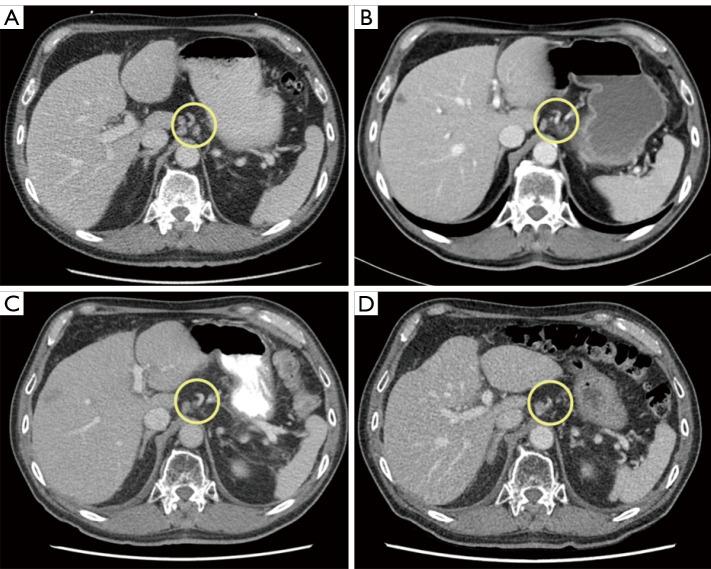

A 75-year-old gentleman with preexisting multivessel CAD was diagnosed with metastatic gastroesophageal junction (GEJ) squamous cell carcinoma (SCC) after presenting to medical attention with a 2-month history of worsening chest pain in addition to progressive dysphagia associated with weight loss. Following initial treatment with palliative locoregional radiotherapy to the lower mediastinum, GEJ, and upper abdomen, the decision was made to proceed with palliative systemic therapy. Considering his significant cardiac history, 5-FU was replaced with raltitrexed and combined with carboplatin and pembrolizumab. After a total of 10 months of treatment, the patient presented to hospital with recurrent chest pain and was diagnosed with a non-ST-elevation myocardial infarction (NSTEMI). Despite radiographic evidence of stability of his malignancy on systemic therapy, he was not considered to be a candidate for cardiac intervention. He was thus transitioned to a comfort-focused care approach and passed away shortly thereafter, with the cause of death being acute coronary syndrome.

一名75岁男性,既往有多支冠状动脉病变,因胸痛加重2个月并伴有进行性吞咽困难和体重减轻前来就医,被诊断为转移性胃食管交界(GEJ)鳞状细胞癌(SCC)。在对下纵隔、GEJ和上腹部进行姑息性局部放疗初始治疗后,决定进行姑息性全身治疗。考虑到他有严重的心脏病史,用雷替曲塞替代5-FU,并与卡铂和帕博利珠单抗联合使用。经过总共10个月的治疗,患者因复发性胸痛入院,被诊断为非ST段抬高型心肌梗死(NSTEMI)。尽管影像学证据显示其恶性肿瘤在全身治疗后病情稳定,但他不被认为是心脏介入治疗的候选人。因此,他转而采用以舒适为重点的护理方法,此后不久去世,死因是急性冠状动脉综合征。